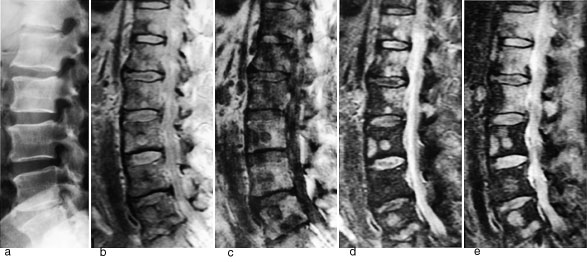

Figur 1 illustrerer det potensialet MR har til å påvise skjelettmetastaser. Protontetthetsbildet viser metastaser klart tydeligere enn det elektrontetthetsbaserte konvensjonelle røntgenbildet. Det T1-vektede bildet viser multiple metastaser med lavt signal, det T2-vektede bildet fremstiller metastasene med høyt signal. STIR (short inversion time inversion recovery)-bildet fremstiller også metastasene med høyt signal. På denne sekvensen summeres effekten av en lang T1 og en lang T2 (typisk for tumor), samtidig med at signalet fra fett er undertrykt. Dette gir sekvensen meget høy sensitivitet.